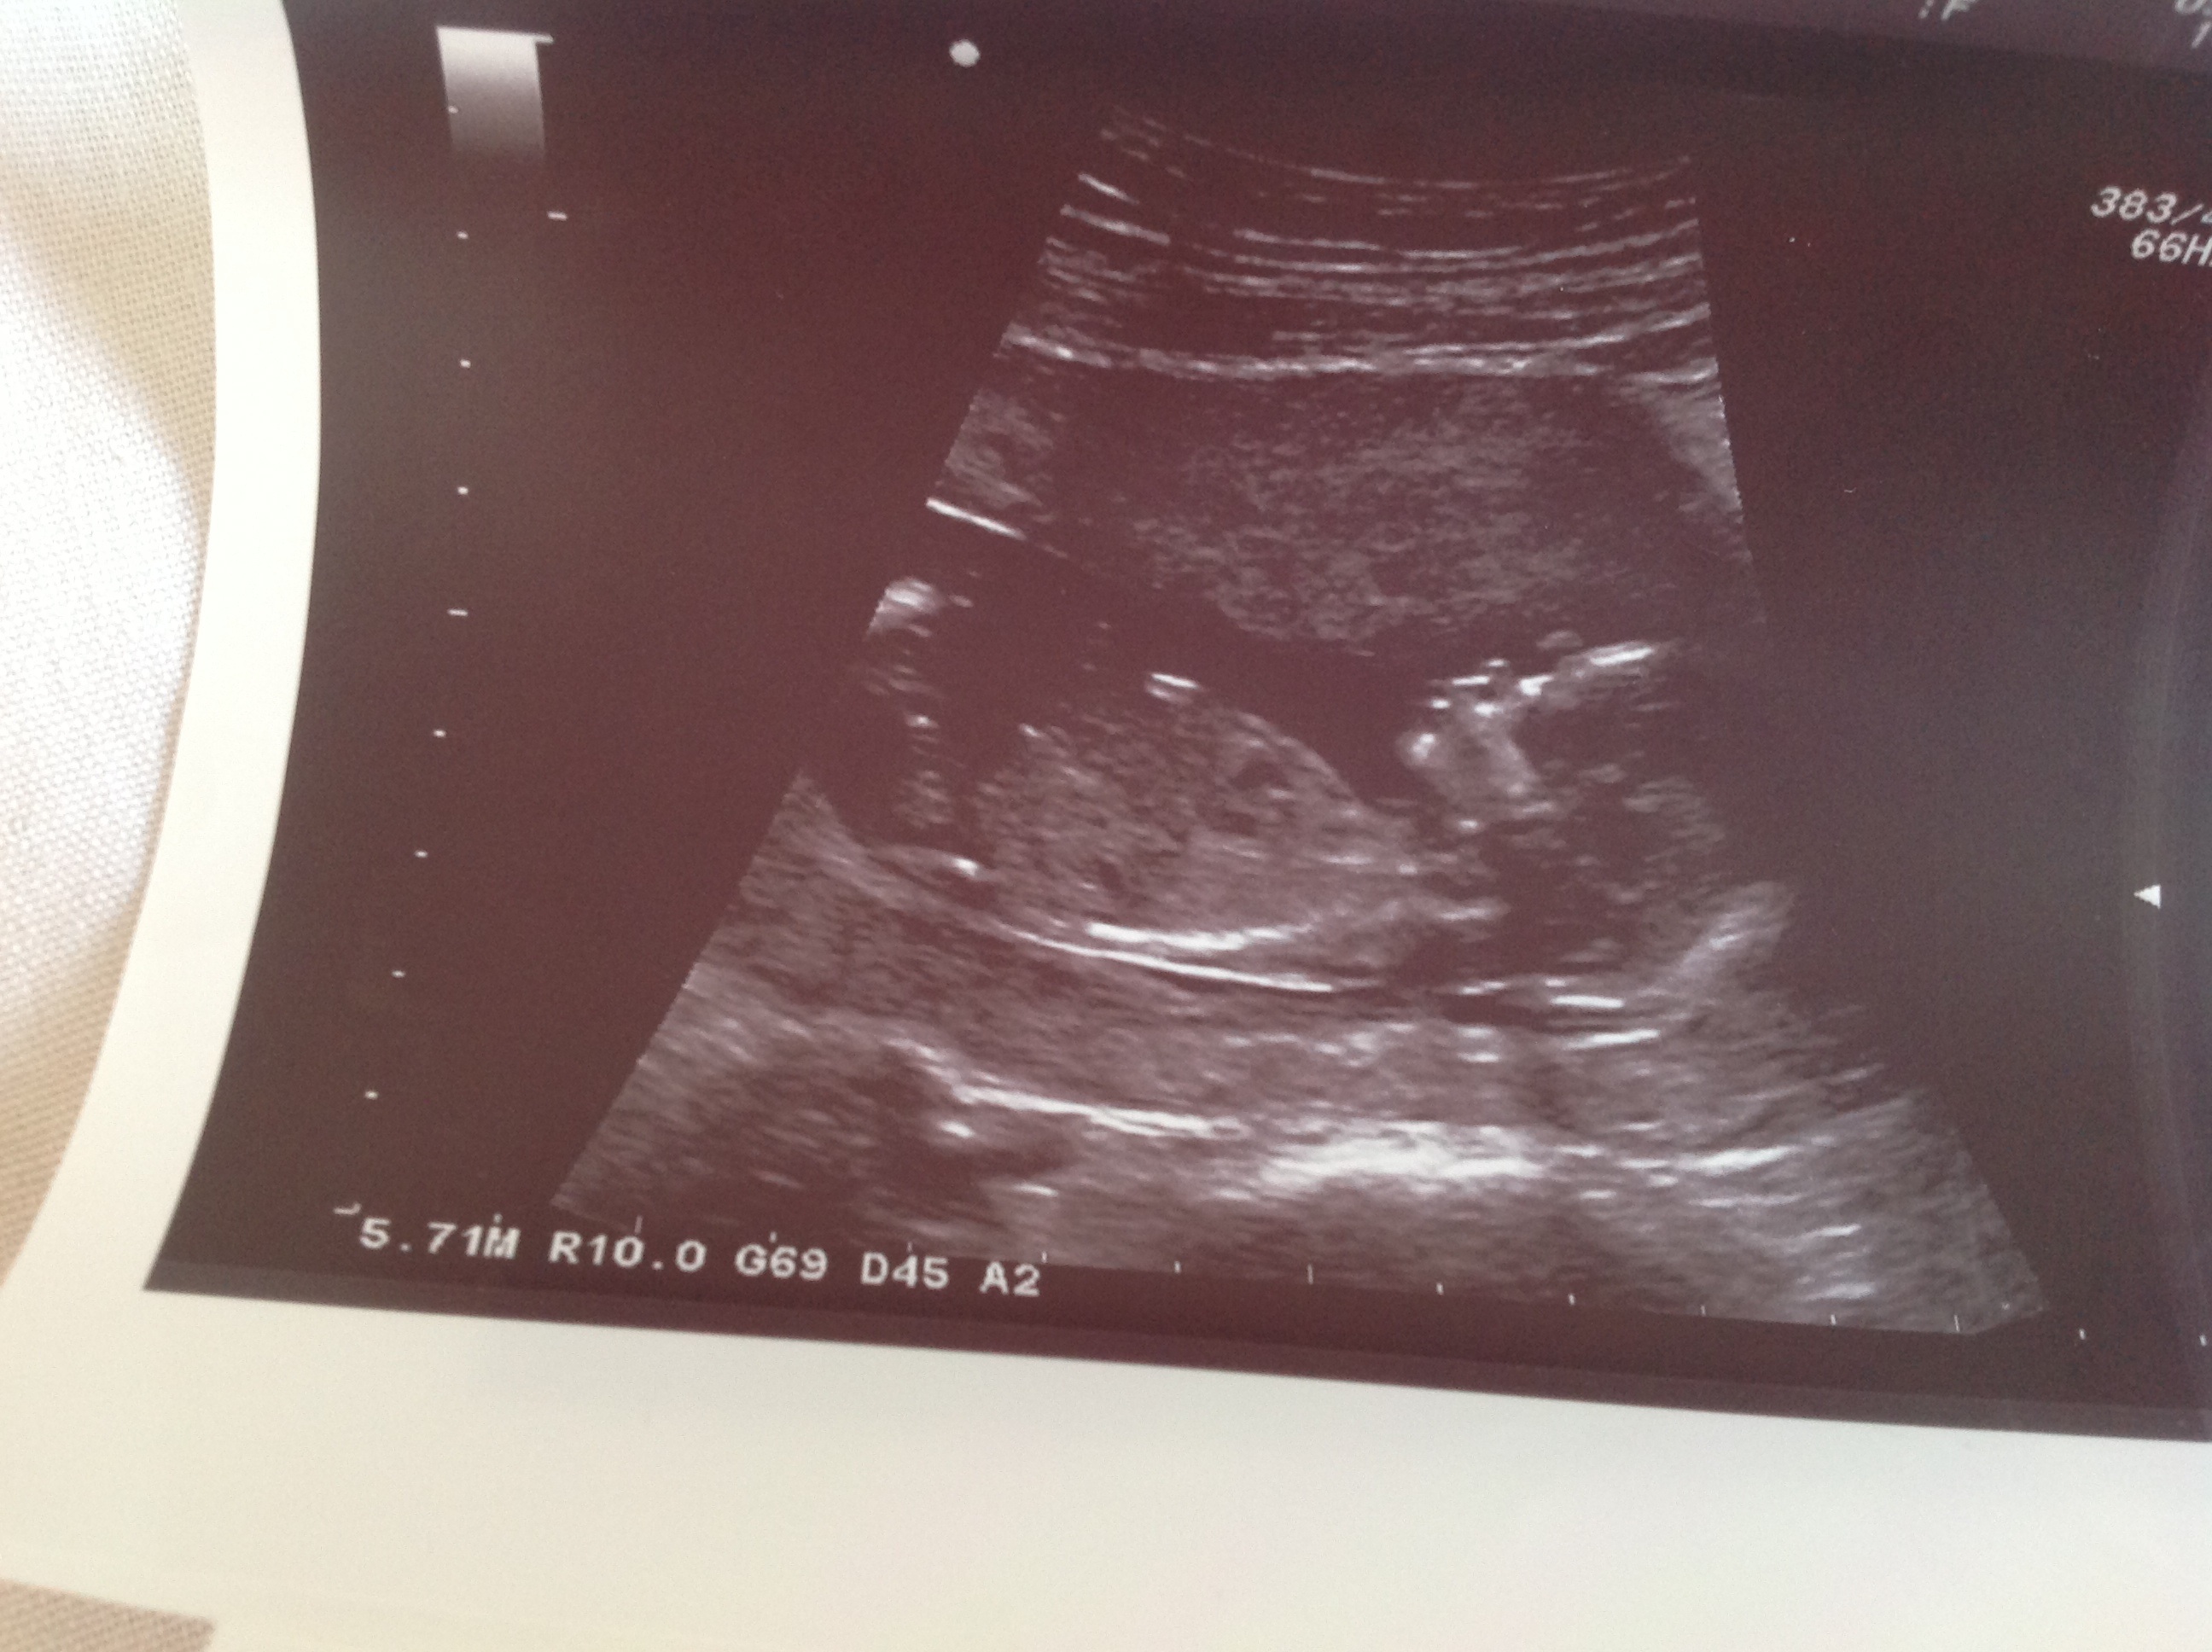

Attachment 11223Attachment 11224

Sorry I can't sew any clues.....congrats on baby tho :)

No nubs :(